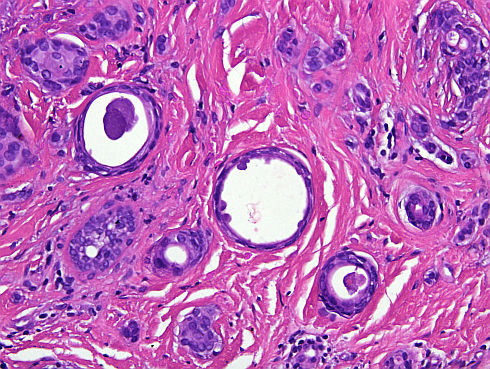

Cas dermatopatologia. Dona de 61 anys amb un àrea hiperqueratòsica vulvar

Març 2013

La biòpsia mostra una proliferació intraepitelial de cèl·lules de nuclis hipercromàtics i citoplasmes clars i abundants. A la porció més basal de dermis es disposen en grups, mentre que a dermis alta apareixen aïllades i són visibles fins i tot a la capa còrnia.

Podria suggerir-se el diagnòstic sense conèixer l'historial clínic?